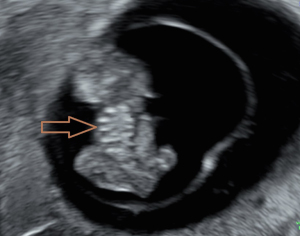

Chief complaint: a 27-year-old gravida presented for routine prenatal ultrasonographic evaluation. Early first-trimester ultrasound surveillance (6 weeks) revealed unremarkable fetal development. The patient denied any pregnancy-associated discomfort at this stage. History: bilateral salpingectomy performed. Personal and family history: the patient had no significant family or genetic history. Physical examination revealed no remarkable findings. All laboratory parameters fell within established normal limits. The patient used ART due to tubal factors. On 16 June 2024, the patient underwent a frozen-thawed blastocyst transfer. The two-dimensional (2D) ultrasound examination at 6 weeks of pregnancy showed a gestational sac in the uterine cavity, with a yolk sac inside and a 0.52 cm-long fetal bud close to the yolk sac, which showed a faint primitive heart tube pulsation. Ultrasound examination at 8 weeks of pregnancy showed a gestational sac in the uterine cavity, with one yolk sac, an amniotic sac, and two fetuses in the gestational sac. One fetus had a crown-rump length of 2.03 cm, and the other fetus had a crown-rump length of 1.88 cm. Both fetuses were consistent with an 8-week pregnancy. Both fetuses demonstrated complete thoracic ectopia cordis with anterior protrusion and cardiac fusion. The sagittal section showed that the two fetuses had a “ball-holding” sign, with a common heartbeat of 169 bpm (Figure 1). The organs above the umbilical part of the two fetuses were connected and protruded towards the front of the abdomen, with a cover on the surface. The cross-section of the chest showed that the two fetuses showed a “dumbbell” sign (Figure 2). The umbilical cords of the two fetuses were fused into a thick umbilical cord, and the entrance end of the umbilical cord abdominal wall was inserted into the fusion of the umbilical cord. The distal end of the umbilical cord was bifurcated and inserted into the placental parenchyma, respectively. Three-dimensional (3D) ultrasound surface imaging intuitively showed the relative positional relationship between the two fetuses and the exposure of the conjoined twins to the heart that fused each other on the outside of the chest cavity (Figure 3). Due to the early gestational week, the anterior diaphragmatic midline of the two fetuses was unclear. The ultrasound machine used in this case was a GE Voluson E10 (GE Healthcare, Chicago, IL, USA), with a RIC5-9-D probe. Figures 4,5 show normal fetus control images at the same gestational age.

With the widespread application of high-resolution transvaginal ultrasound, visualization of early pregnancy has become possible. The accuracy of assessing the risk of fetal chromosomal abnormalities through early pregnancy ultrasound combined with biochemical markers has improved, leading to the diagnosis of more fetal abnormalities in the early stages of pregnancy. A study indicated that ultrasound diagnosis of conjoined twins typically occurs between 11 and 13 weeks and 6 days. Screening at this stage can detect the most severe fetal malformations (8). There are reports that high-resolution ultrasound has advanced the diagnosis of conjoined twins to 7 weeks of gestation. However, due to the early gestational age, it is difficult to precisely determine the specific type of connection between the twins, and color Doppler ultrasound is typically required to assist in diagnosing the presence of conjoined twins (9). Fetal development is a process, and it can only be detected by ultrasound once it has reached a distinguishable gestational age. When fetal activity increases, around 8 weeks of gestation, it becomes easier to distinguish between monochorionic twins and conjoined twins (10). The patient underwent an ultrasound examination at 6 weeks of gestation, during which only a small, short, line-like embryonic bud and weak fetal heartbeat were observed. During the ultrasound examination at 8 weeks of gestation, we discovered that the two fetuses were embracing a “spherical” structure. The sagittal section revealed the “ball-holding” sign, and the transverse section showed a notch at the junction of the thoracic and abdominal walls, presenting the “dumbbell” sign. These two signs are specific to thoracoabdominal conjoined twins, with both fetuses affected by Cantrell’s pentalogy. Transvaginal 2D and 3D ultrasound provides direct evidence for the early identification of a special type of conjoined twins and advances the diagnostic gestational age to 8 weeks. Through transvaginal 2D ultrasound, the issue was identified, followed by adjusting the probe direction and angle to locate the specific connection site of the conjoined twins and determine the type of connection. The multiplanar views of 3D ultrasound provide additional detailed information. Adjusting the direction of light incidence, rotating the probe at multiple angles, and adjusting the 3D image, combined with surface imaging mode, yields more detailed features. The combination of 2D and 3D ultrasound provides more information than 2D ultrasound alone, offering more intuitive images, particularly suitable for fetuses with abnormal external features. A study has confirmed the role of 3D ultrasound in diagnosing prenatal abnormalities, which is consistent with our findings (11).

Ventral body wall defects represent a spectrum of malformations, likely caused by disrupted mesodermal development during early embryogenesis (days 14–19), followed by failed diaphragmatic crossing (12). These defects arise from abnormal closure of the ventral body wall folds and are present in various combinations, the most severe of which is Cantrell’s pentalogy. First described by Cantrell et al. in 1958, this syndrome comprises five congenital anomalies: cardiac, pericardial, sternal, diaphragmatic, and anterior abdominal wall defects, with an estimated incidence of 1 in 65,000 to 1 in 200,000 live births (4). The hallmark features of Cantrell’s pentalogy are ectopia cordis and omphalocele. Thoraco-abdominal schisis manifests as partial or complete displacement of the heart out of the thoracic cavity. An omphalocele is another common manifestation, wherein the abdominal contents protrude through the anterior abdominal wall, covered by a thin membrane. Sternal defects may present as a partial or complete absence of the xiphoid process of the sternum. Diaphragmatic defects involve congenital or acquired fissures in the diaphragmatic structure. Although pericardial defects are generally less severe and rarely life-threatening, they may occasionally lead to complications such as pericardial effusion. Cardiac defects such as atrial septal defect, transposition of the great arteries, pulmonary valve stenosis, and tetralogy of Fallot are associated with Cantrell’s pentalogy. Some researchers classify Cantrell’s pentalogy into three types based on the type of defect: (I) complete syndrome involving all five defects; (II) four defects including the sternum and anterior chest wall; and (III) incomplete type involving various combinations of defects, including sternal abnormalities (13). The ultrasound examination of this case revealed significant cardiac ectopia and omphalocele. The shared heart and abdominal organs of the two fetuses were fused and protruded through the thoracic wall toward the anterior thoracoabdominal wall. The sternum was not visible. The early stage of gestation precluded definitive characterization of the specific diaphragmatic and cardiac malformations. Cardiac ectopia, omphalocele, thoraco-abdominal schisis, and an unseen sternum showed direct signs of conjoined twins, and both fetuses were associated with incomplete Cantrell’s pentalogy. A key limitation in early prenatal diagnosis of conjoined twins with Cantrell’s pentalogy is the early gestational age, when incomplete fetal organ development may obscure the detection of associated structural abnormalities.